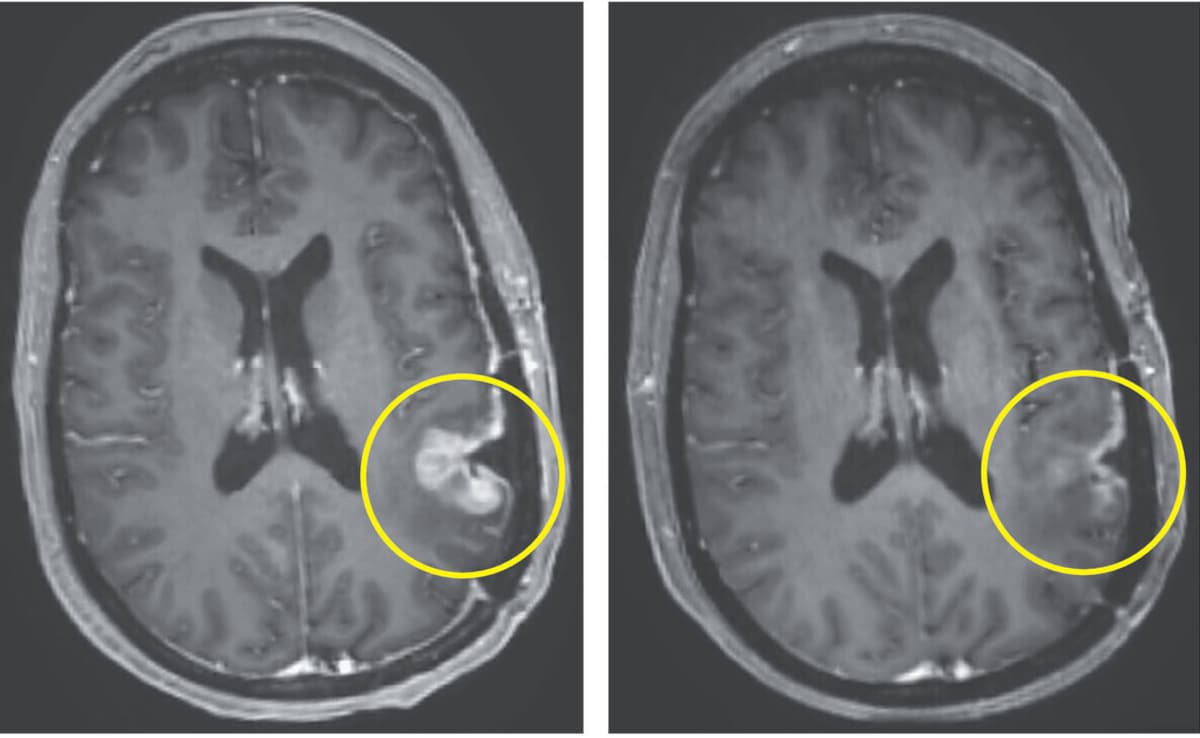

Breakthrough Brain Cancer Therapy Shows Dramatic Tumour Shrinking In 5 Days In Early Trial